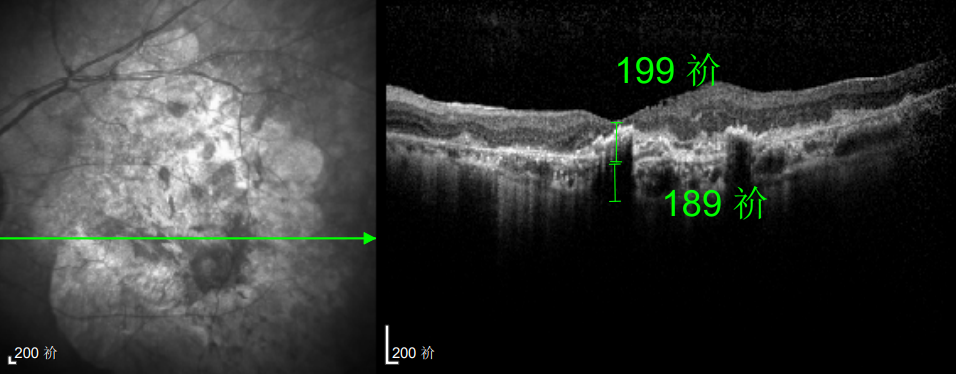

△延誤復(fù)查后的左眼

△規(guī)劃化治療后的左眼